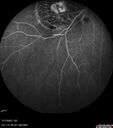

Severe NPDR with non-perfusion on FA18 views64 year old man with 20/32 vision in both eyes and mild blurring. FA shows non-perfusion but no proliferationNov 23, 2025

Severe NPDR with non-perfusion on FA27 views64 year old man with 20/32 vision in both eyes and mild blurring. FA shows non-perfusion but no proliferationNov 23, 2025

Severe NPDR with non-perfusion on FA26 views64 year old man with 20/32 vision in both eyes and mild blurring. FA shows non-perfusion but no proliferationNov 23, 2025

Severe NPDR with non-perfusion on FA29 views64 year old man with 20/32 vision in both eyes and mild blurring. FA shows non-perfusion but no proliferationNov 23, 2025

Severe NPDR with non-perfusion on FA37 views64 year old man with 20/32 vision in both eyes and mild blurring. FA shows non-perfusion but no proliferationNov 23, 2025